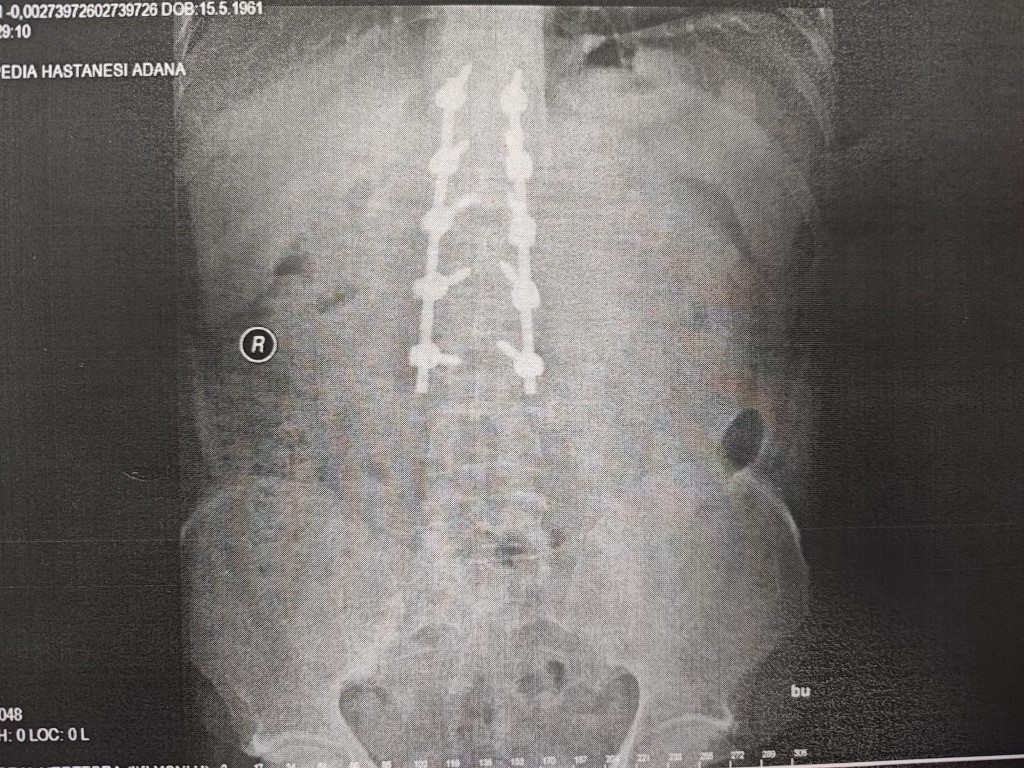

Aras, teknik hata yüzünden ölümden döndüğünü 10 platin ile yaşamak zorunda kaldığını belirterek, “Ortalama 3 ay boyunca tedavi sürecim devam etti. Omurga kemiğim kırıldı ve şuan hala 6 buçuk santim boyunda 10 tane çelik platin var. Dik durabilmem için çelik vidalar var. Ancak onların sayesinde ayakta durabiliyorum. 2019 yılında meydana geldi kaza ve bana araba artı para teklif ettiler. Bende, aynı arabanın birebir aynısı ya da bir üst modeliyle değiştirilmesini istedim. İlk önce bir alt modelini vermeyi teklif ettiler. Üstüne de para verelim dediler. Ben bunları kabul etmedim, zararımın giderilmesini istiyorum. Bayiyi hurda parça takmaktan dolayı şikayet ettim. Arabayı imal eden Mercedes’i de dava ettim” diye konuştu.